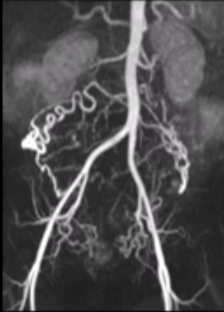

子宫动脉栓塞治疗子宫肌瘤已成为针对此类患者的一种重要且往往能带来重大改变的治疗手段。这些患者因各种严重的症状(如严重的排尿障碍到月经过多)而被转介至各类医疗机构接受治疗。 也有患者因为复发需要接受二次子宫肌瘤动脉栓塞,甚至多次治疗。再治疗率达到了 5%左右。 重要预测因素: 卵巢动脉的供血识别 子宫肌瘤的大小/体积以及子宫的大小/体积 血管供应的范围 复杂的解剖结构 技术方面的问题包括避免痉挛、选择合适的栓塞物等。 发现卵巢动脉供血

成功的栓塞治疗取决于对术前磁共振成像(MRI)结果的仔细分析和标准化处理。重复进行干预治疗最常见的指征是左侧卵巢动脉供血。。 | ||||||||||||||